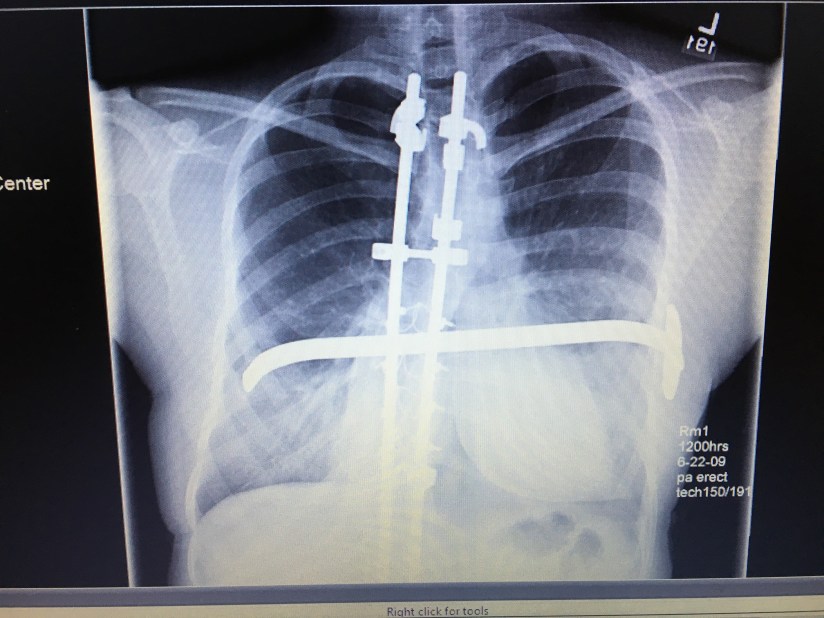

At my physical before entering 7th grade, the doctor noticed that my spine was curved – pretty severely. An X-ray showed a 72 degree curve in my upper spine. A back brace was out of the question and I was scheduled to have spinal fusion surgery in April of my 7th grade year. Leading up to my surgery was miserable. No matter how I sat in a desk, I was in horrible pain at school. Kids are already mean at that age and I tried to keep a sense of humor about it, but the comments about being a “hunchback” and looking like Quasimodo hurt.

My surgery lasted 14 hours and I was in the hospital for about a week. I woke up from surgery two inches taller and that was the height I would stay the rest of my life. I couldn’t return to school until 8th grade and I was pretty much bed-ridden for that whole summer.